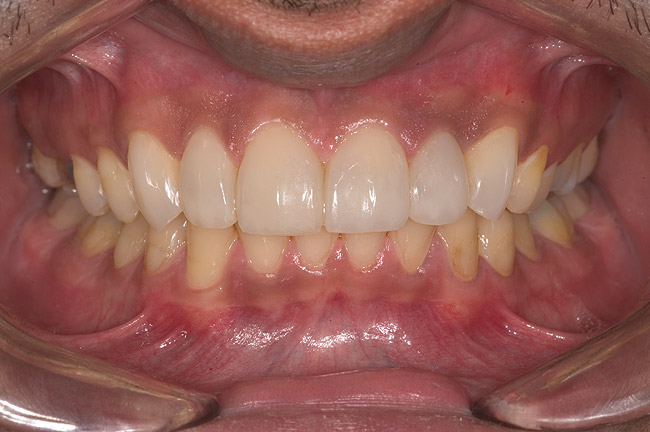

Figure 14  Postoperative smile.

Figure 14